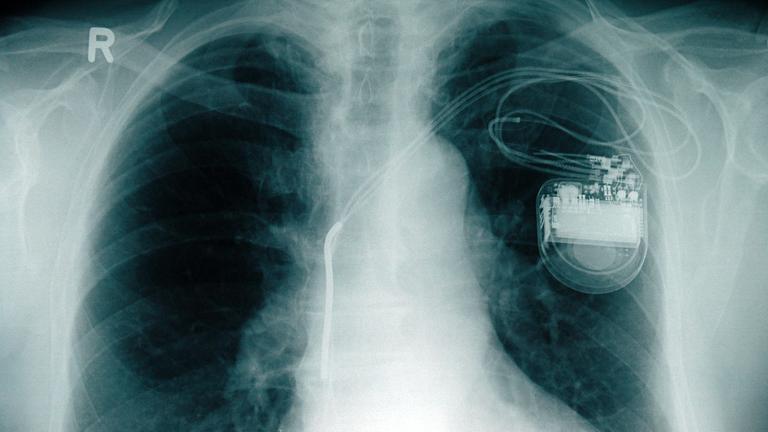

2. Archivfoto-Illustration: Röntgenbild mit Herzschrittmacher

Was im Alltag wichtig ist:Herzschrittmacher als neuer Schritt ins Leben